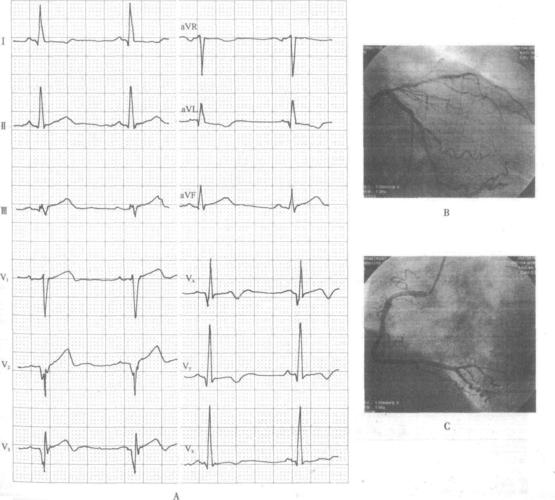

前降支近段病变致急性前壁心肌梗死-精编心电图诊断

心电图定位之前降支阻塞